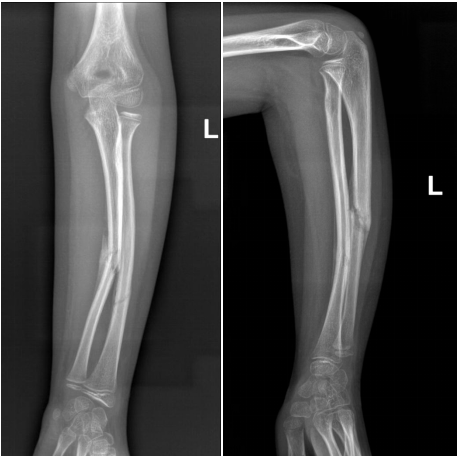

7岁的黎同学

上学时不慎摔倒

导致左前臂疼痛畸形

当地医院X片提示

“左侧尺桡骨干骨折”

术前骨折断端移位明显

经手法复位治疗无效